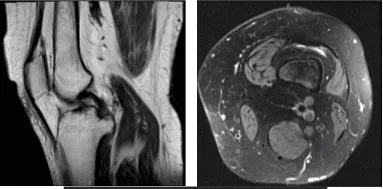

Patient MRI showed significant results. Impression as follows: Vertically oriented tear of the posterior horn medial meniscus extending to the posterior root attachment of the junction of the inner and central thirds.

Shallow fraying of the undersurface of the medial meniscal body. Mild MCL sprain. Mild to moderate chondromalacia patella as well as cartilage loss at the periphery of the lateral trochlea. Joint effusion and thickened medial parapatellar plica.

MRI-3T Left knee non-contrast